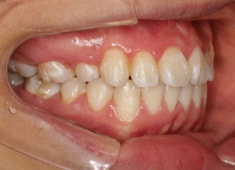

治療開始から11ヶ月後